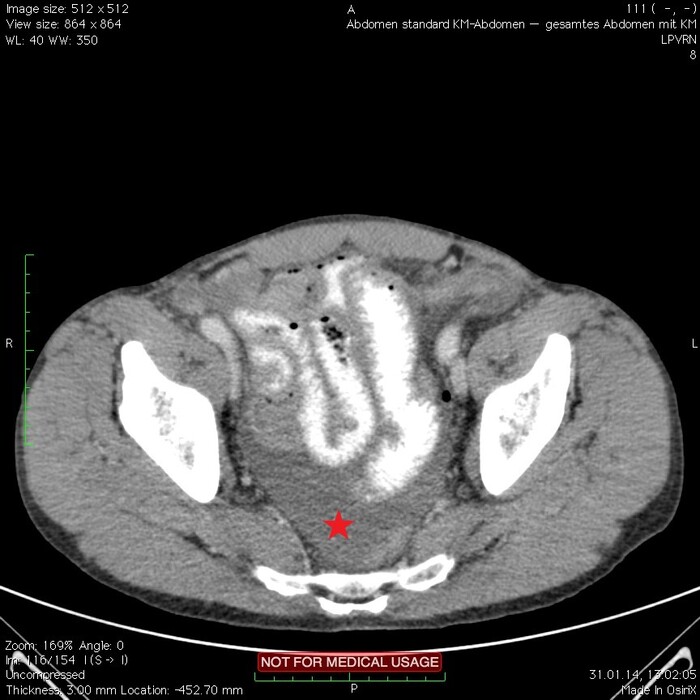

Мужчина, 32 года. Во время игры в футбол получил удар в низ живота, игру продолжил. Впоследствии боли в животе усиливались, стали нестерпимыми, ухудшилось общее самочувствие. На следующий день после игры пошёл сдаваться в больницу. Хирурги клинически описывают разлитой перитонит (воспаление брюшины) и отсылают пациента к нам на КТ, которое мы провели с внутривенной дачей контраста + заставили контраст ещё выпить (специальный раствор для перорального применения).

Так как клиника у нас острого живота после тупой травмы, учитывая что боли во всём животе и признаков большой кровопотери нет, то первое, что ищем - это свободный газ в брюшной полости, и находим его! (для этого лучше всего подходит т.н. лёгочное окно, как представлено ниже, или можно искать в костном окне - это спец.настройки яркости и контраста для просмотра разных структур тела - лёгкие, мозг, мягкие ткани, кости):

Отмечаем про себя, что в верхних квадрантах свободного газа не так уж и много. При перфорации желудка газа намного больше. Также выясняем, что газ есть также и в нижних квадрантах:

Ещё бросается в глаза массивный выпот (стрелки) во всех этажах, а также утолщение брюшины на всём протяжении, что указывает на диффузный (разлитой) перитонит. Тут, кстати, уже мягкотканное окно:

Итак, имеет место быть свободный газ в брюшной полости + свободная жидкость + перитонит. Определённо перфорация! Осталось найти источник. Желудок не подходит по механизму, а точнее по локализации травмы. Мочевой пузырь - в нём нет воздуха. Остаётся методом исключения только кишечник. Толстый или тонкий? Явно не верхние отделы толстого кишечника (ободочная кишка в области печеночного и селезеночного углов, а также поперечная исключаются - было бы больше воздуха). Сигма и нисходящая тоже заполнены стулом и воздухом. Получается, что тонкий кишечник всему виной.

Верхние (проксимальные) отделы точно не причём. Жидкость (звёздочки) больше в малом тазу, тут же и воздух. Для сравнения верхний этаж:

Hижний этаж:

И тут СТОП! А это чтo такое???

Кишке это точно не принадлежит, как ни крути. Это вышедший за пределы кишки контраст, который пациент выпил!

Осталось только место выхода найти:

Итого: перфорация тощей кишки в дистальных отделах, разлитой перитонит.

Был успешно прооперирован, место перфорации ушито, выписан.